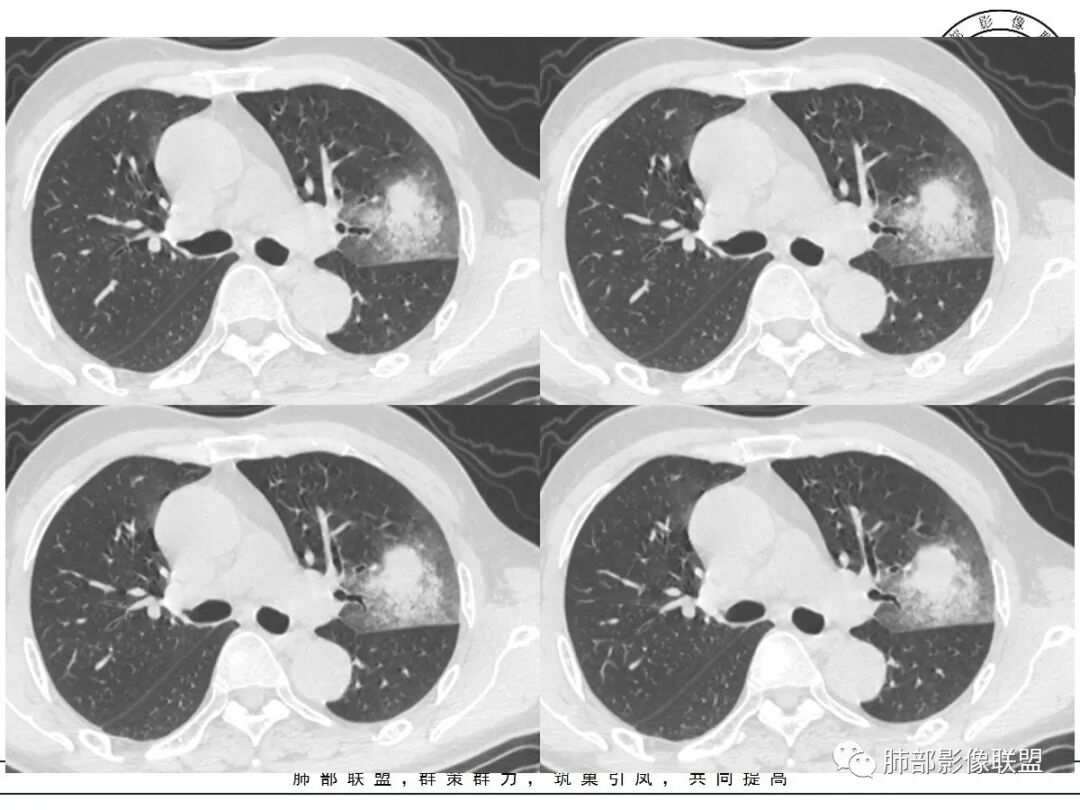

左肺上叶类圆形软组织影,边界较清楚,其内密度均匀,外侧缘可见空气新月征,并可见点状钙化,增强扫描可见均匀强化,病灶周围可见磨玻璃渗出性密度影,斜裂侧光滑平整。考虑炎性病灶,以肉芽肿性炎症为主(如真菌性肉芽肿),鉴别结核(无卫星灶,无多态性),肺癌(无毛刺,分叶等恶性征象,)细菌性炎症(密度一般不这么致密,很少钙化及空气新月征)。

左肺上叶类圆形软组织影,界清,内见空洞影,病灶周围斑片影,可见空气支气管征,未垮叶。考虑炎性病变,糖尿病四大金刚,肺克?毛霉?

老年男性,血糖升高六年,反复咳痰咳嗽3周,左肺上叶近斜裂类圆形肿块影,边缘伴磨玻璃影,边界不清。内部可见支气管走行、钙化、小空洞,叶间裂局部膨隆,增强扫描轻度强化,内部可见小的低密度区,边界尚清。考虑为炎性病变可能性大。

左肺叶裂旁实变影,宽基底与叶裂胸膜相连,边缘平直,部分略膨隆,病灶近段及上段支气管深入病灶内,部分壁略增厚,远端支气管截断,似有小空泡,壁规则,内部可见高密度钙化,周围可见模糊的GGO,血象正常,考虑结核(NTM),鉴别隐球菌,奴卡,放线菌。

老年男性,66,反复咳嗽、咳痰3月。糖尿病,血象不高。

胸部CT:左肺上叶类圆形肿块影,边界较清楚,密度较均匀,内可见小片坏死、偏心空洞、空气新月征、点状钙化,周围晕、絮状渗出、边缘模糊,支气管扩张、充气征、支气管进入病灶堵塞,叶裂牵拉明显,增强扫描中度均匀强化,纵隔可见淋巴结。考虑:炎性病灶,肉芽肿性炎症,曲霉?毛霉?鉴别:TB,淋巴瘤。

左上肺类圆形肿块影,边界较清楚,支气管通畅略扩张,周围磨玻璃影,其内密度均匀,外侧见空气新月征,且见点状钙化。叶间裂光滑稍膨隆。老年男性,糖尿病,高血压,痰培养克雷伯菌。综合考虑炎性病灶,克雷伯合并真菌感染,曲霉。结核合并真菌。鉴别肺癌合并感染。

左肺上叶类圆形软组织影,边界稍模糊,其内密度均匀,外侧缘可见空气新月征,并可见点状钙化,增强扫描渐进性强化,病灶周围可见磨玻璃影,斜裂侧光滑平整,气管未见明显闭塞,淋巴结未见肿大,糖尿病患者,首先考虑感染性变,结核并曲霉?